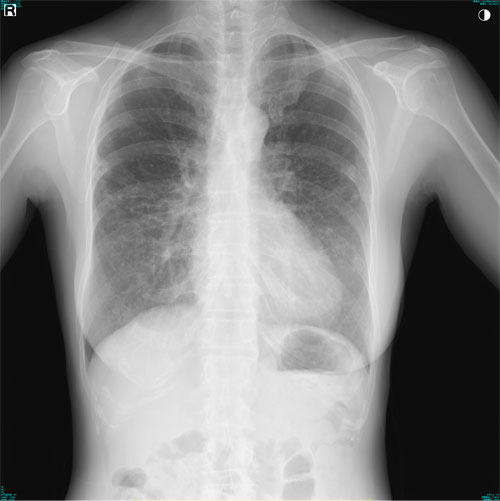

肺X線画像

- 2023.07.27 肺炎と診断された画像(国立系病院)